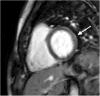

We report the case of a 40-year-old veterinary surgeon who was admitted for spiking fevers, arthralgia, and a complete atrioventricular block. Tests revealed an inflammatory syndrome, hepatic cytolysis, neutrophilic leukocytosis, and increased troponin levels. Cardiac magnetic resonance imaging showed a small myocarditis but no tissue abnormality on the conduction pathways. In the absence of evidence-based infection and favorable evolution under broad spectrum antibiotherapy, an adult-onset Still's disease was suspected and corticosteroid therapy administered. Evolution was then impressively favorable, with a persistent sinus heart rhythm 3 days later. Learning objective: Febrile conductive disorders occurring during a systemic disorder with negative infection and auto-immunity work-up should lead to consider an adult-onset Still's disease, which can be treated and cured, especially with steroids. Moreover, fever, polyarthritis, neutrophilic leukocytosis, pericarditis, and myocarditis should lead to consideration of adult-onset Still's disease.